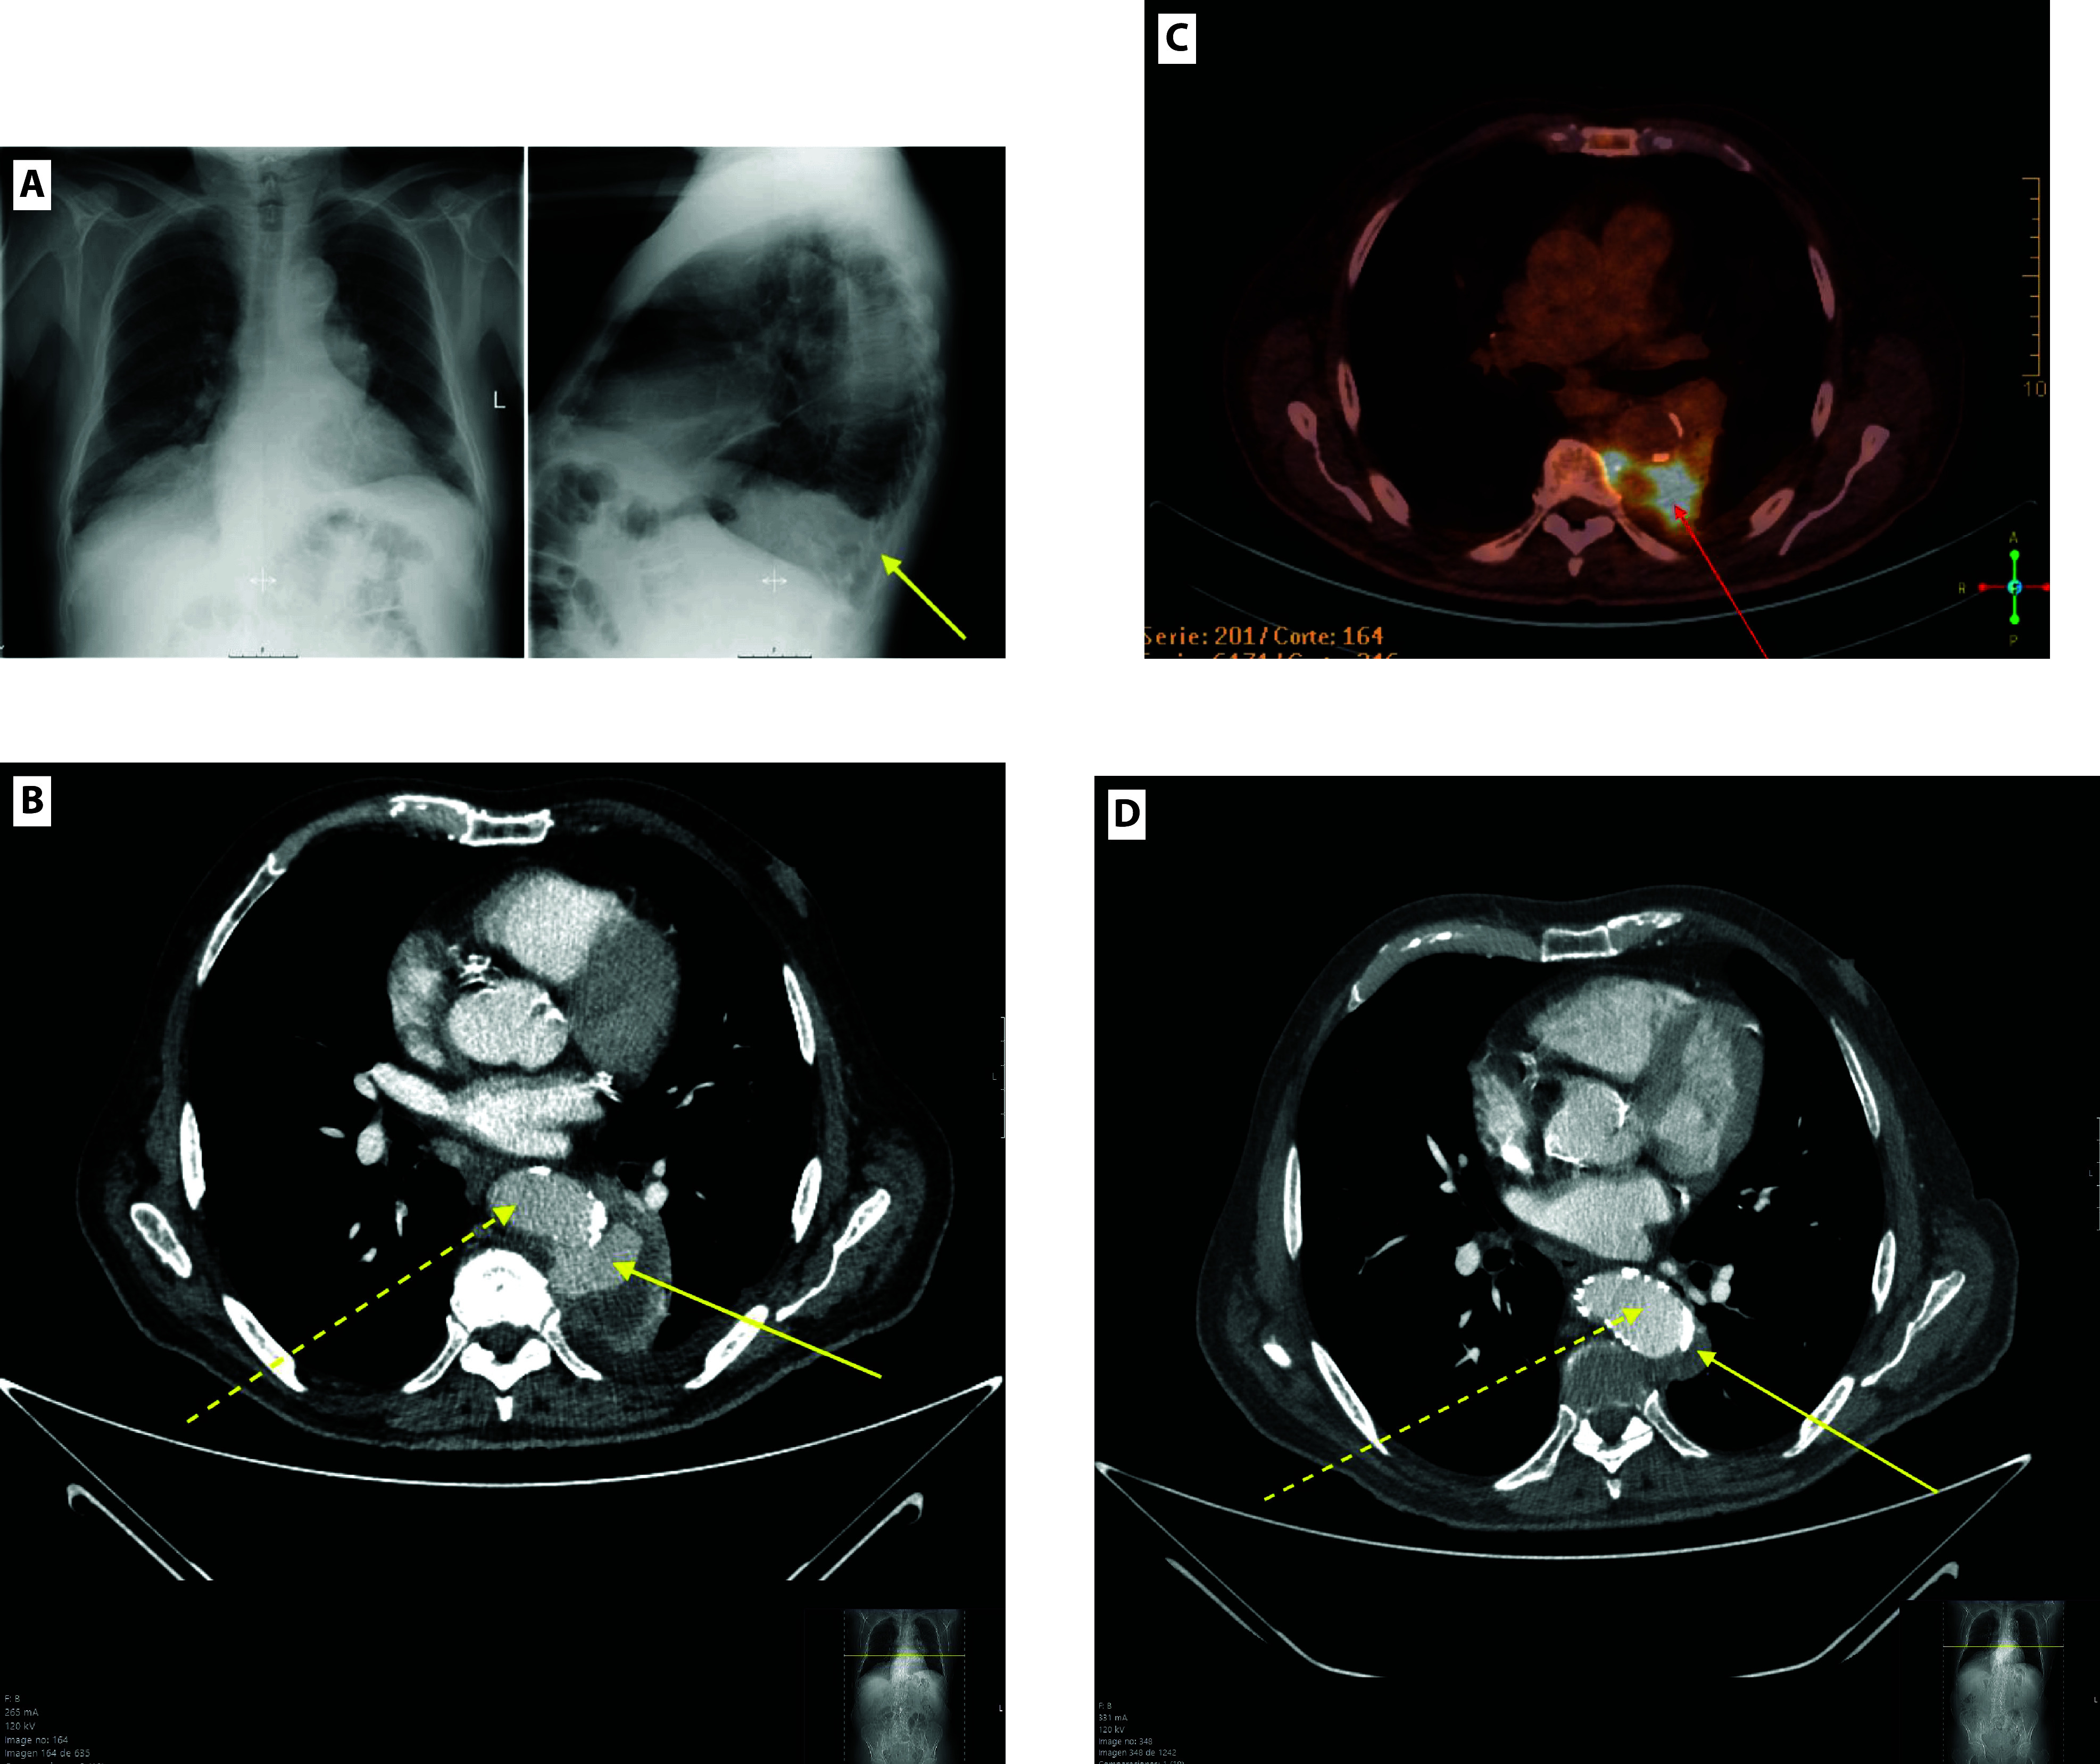

Case presentation: We report the case of an 81-year-old male who presented with fever and pleuritic chest pain and was initially misdiagnosed with community-acquired pneumonia. A CT scan later  revealed a saccular, ruptured thoracic aortic aneurysm. Despite antibiotic therapy, the patient developed haemoptysis, necessitating thoracic endovascular aortic repair (TEVAR). Post-procedure, the patient showed significant clinical improvement and was discharged in stable condition 45 days later.